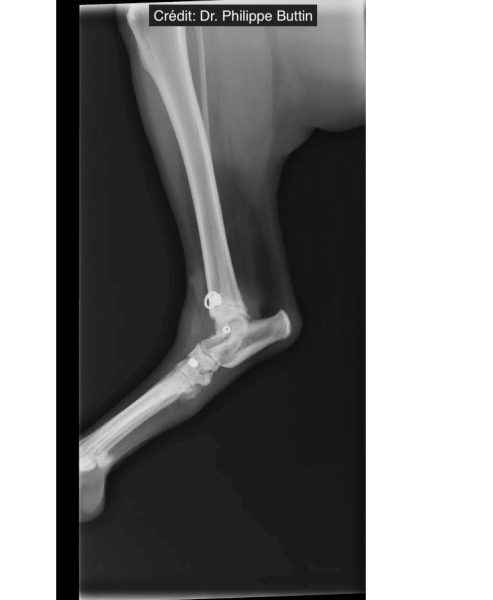

Reconstruction of tarsal medial collateral ligament

Radiologické snímky

Achilles Tendon Repair